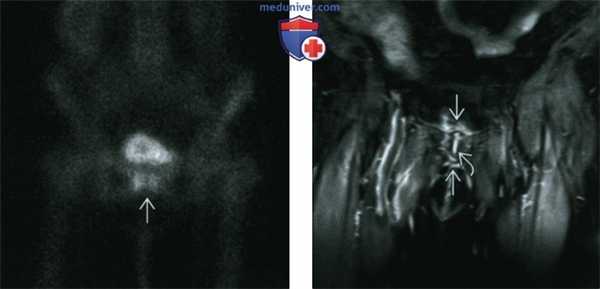

(Слева) Сканирование костей скелета в прямой проекции: определяется часто обнаруживаемое повышение поглощения по обе стороны от лобкового сочленения. До тех пор, пока в этой области не появятся симптомы, эти изменения обычно относят к последствиям дегенеративного заболевания.

(Справа) МРТ, STIR, корональный срез: определяется жидкость в лобковом симфизе и воспалительные изменения в капсуле сустава и прилегающих мягких тканях. Наблюдается легкий отек костного мозга по обе стороны сочленения. Эти признаки нередко встречаются у пациентов пожилого возраста.